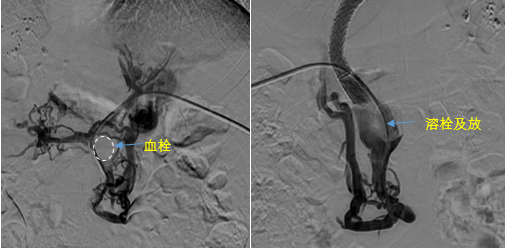

在西安國際醫(yī)學(xué)中心醫(yī)院,韓國宏教授對李女士進(jìn)行了細(xì)致的問診及檢查,在CT圖像上仔細(xì)的分析,針對患者特殊的病情制定了詳細(xì)的治療方案。第一次進(jìn)入手術(shù)室,在DSA的監(jiān)測下,造影過程中門靜脈血栓的輪廓逐漸顯現(xiàn)出來,見多識廣的醫(yī)生們也大吃一驚,發(fā)現(xiàn)遠(yuǎn)端脾靜脈及腸系膜上靜脈也存在大量血栓?;颊叩氖彻芪傅嘴o脈曲張非常嚴(yán)重,疏通堵塞的門靜脈已是刻不容緩。

見此情形,韓國宏教授憑借豐富的臨床經(jīng)驗很快調(diào)整了策略,在超聲診療中心的協(xié)助下進(jìn)行門靜脈右支穿刺,并進(jìn)行造影,看到目標(biāo)血管后,韓國宏教授用“明修棧道,暗渡陳倉”的方法,讓來自脾臟和胃腸的血流終于暢通的回流到了肝靜脈。通過血流的沖刷以及抗凝溶栓藥物的作用,幾日后復(fù)查造影發(fā)現(xiàn)門靜脈血栓已逐漸變小,不會對回流到肝臟的血流產(chǎn)生大的阻礙作用,門靜脈的壓力顯著減小,患者再次出血的幾率也隨之降低。幾經(jīng)周折,這顆“定時炸彈”終于被拆除,李女士和她的家人多年來心里的石頭也終于落地。